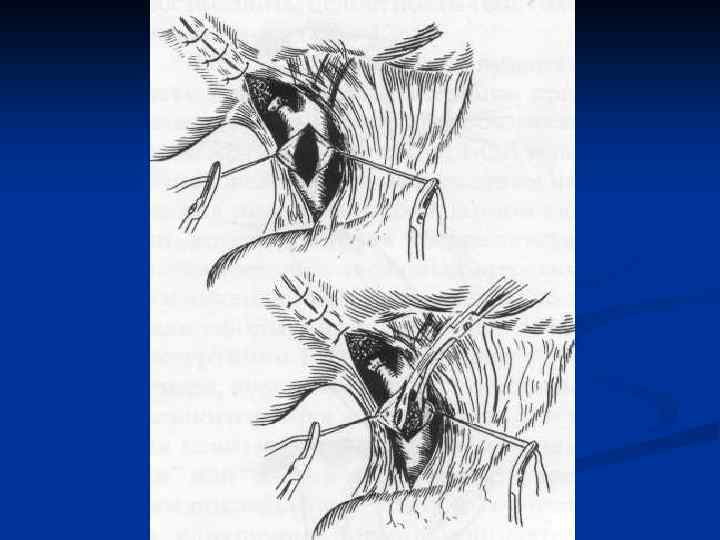

Лечение холангиолитиаза Холангиолитиаз устраняется с помощью эндоскопических методов после выполнения РХПГ. Выполняется эндоскопическая папиллосфинктеротомия в сочетании с удалением камней из холедоха петлей Дормиа, катетером Фогарти n Лапаротомия с холедохотомией – альтернативный метод лечения. n

Лечение холангиолитиаза Холангиолитиаз устраняется с помощью эндоскопических методов после выполнения РХПГ. Выполняется эндоскопическая папиллосфинктеротомия в сочетании с удалением камней из холедоха петлей Дормиа, катетером Фогарти n Лапаротомия с холедохотомией – альтернативный метод лечения. n